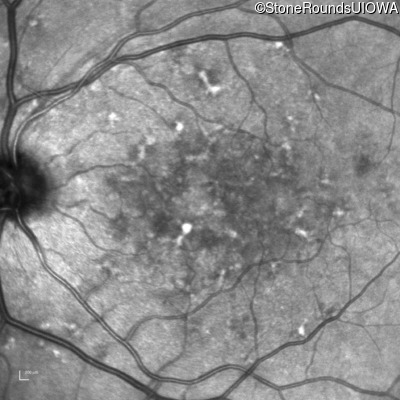

Infrared Fundus Photograph - Right - 20/250

Exemplar